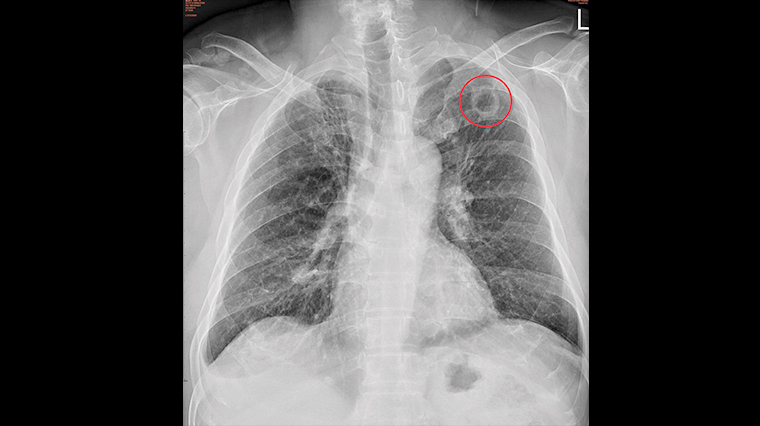

【NOW健康 陳郁茹/台中報導】台中1名56歲的盧先生,本身有糖尿病史與抽菸習慣,前陣子確診,在痊癒後卻仍持續咳嗽,原本他不以為意,直到後來周遭人群投來異樣眼光,懷疑他在散播病毒,才到胸腔內科門診就醫。烏日林新醫院胸腔內科醫師許人文表示,患者X光檢查中左上肺有一個2.5公分的空洞,雖然痰液抹片結核菌為陰性,但電腦斷層掃描判定為肺結核菌所造成,目前病人已接受抗結核藥物治療,並通報衛生單位。

▲烏日林新醫院胸腔內科醫師許人文指出,從患者X光檢查中發現左上肺有一個2.5公分的空洞。(圖/烏日林新醫院提供)